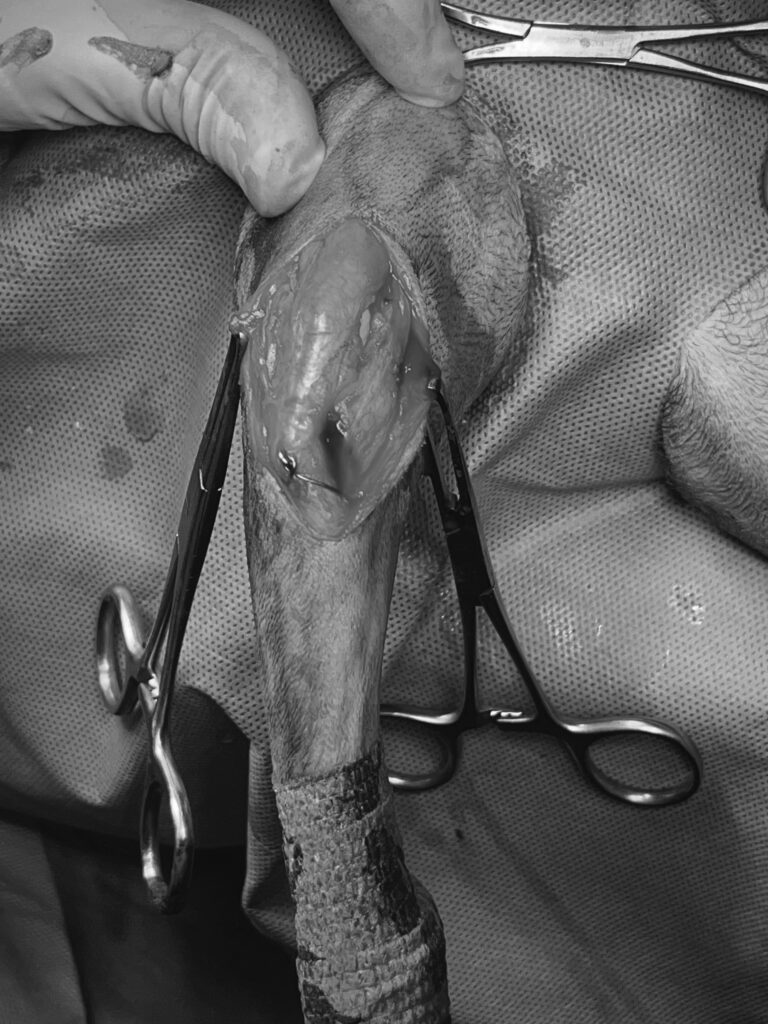

수술사진(좌) / 수술 후 관절주사 주입사진(우) / 출처: 라온동물메디컬센터

환자는 계획된 일정에 따라 양측 슬개골 교정 수술을 진행했습니다.

라온동물메디컬센터는 수술 후 애니콘 주(Anicon Inj.) 관절 주사를 병행하여 수술 시 통증 완화와 빠른 회복에 힘쓰고 있습니다.

수술 과정은 순조롭게 진행되었으며, 출혈이나 감염 등 합병증 없이 안정적으로 마무리되었습니다.